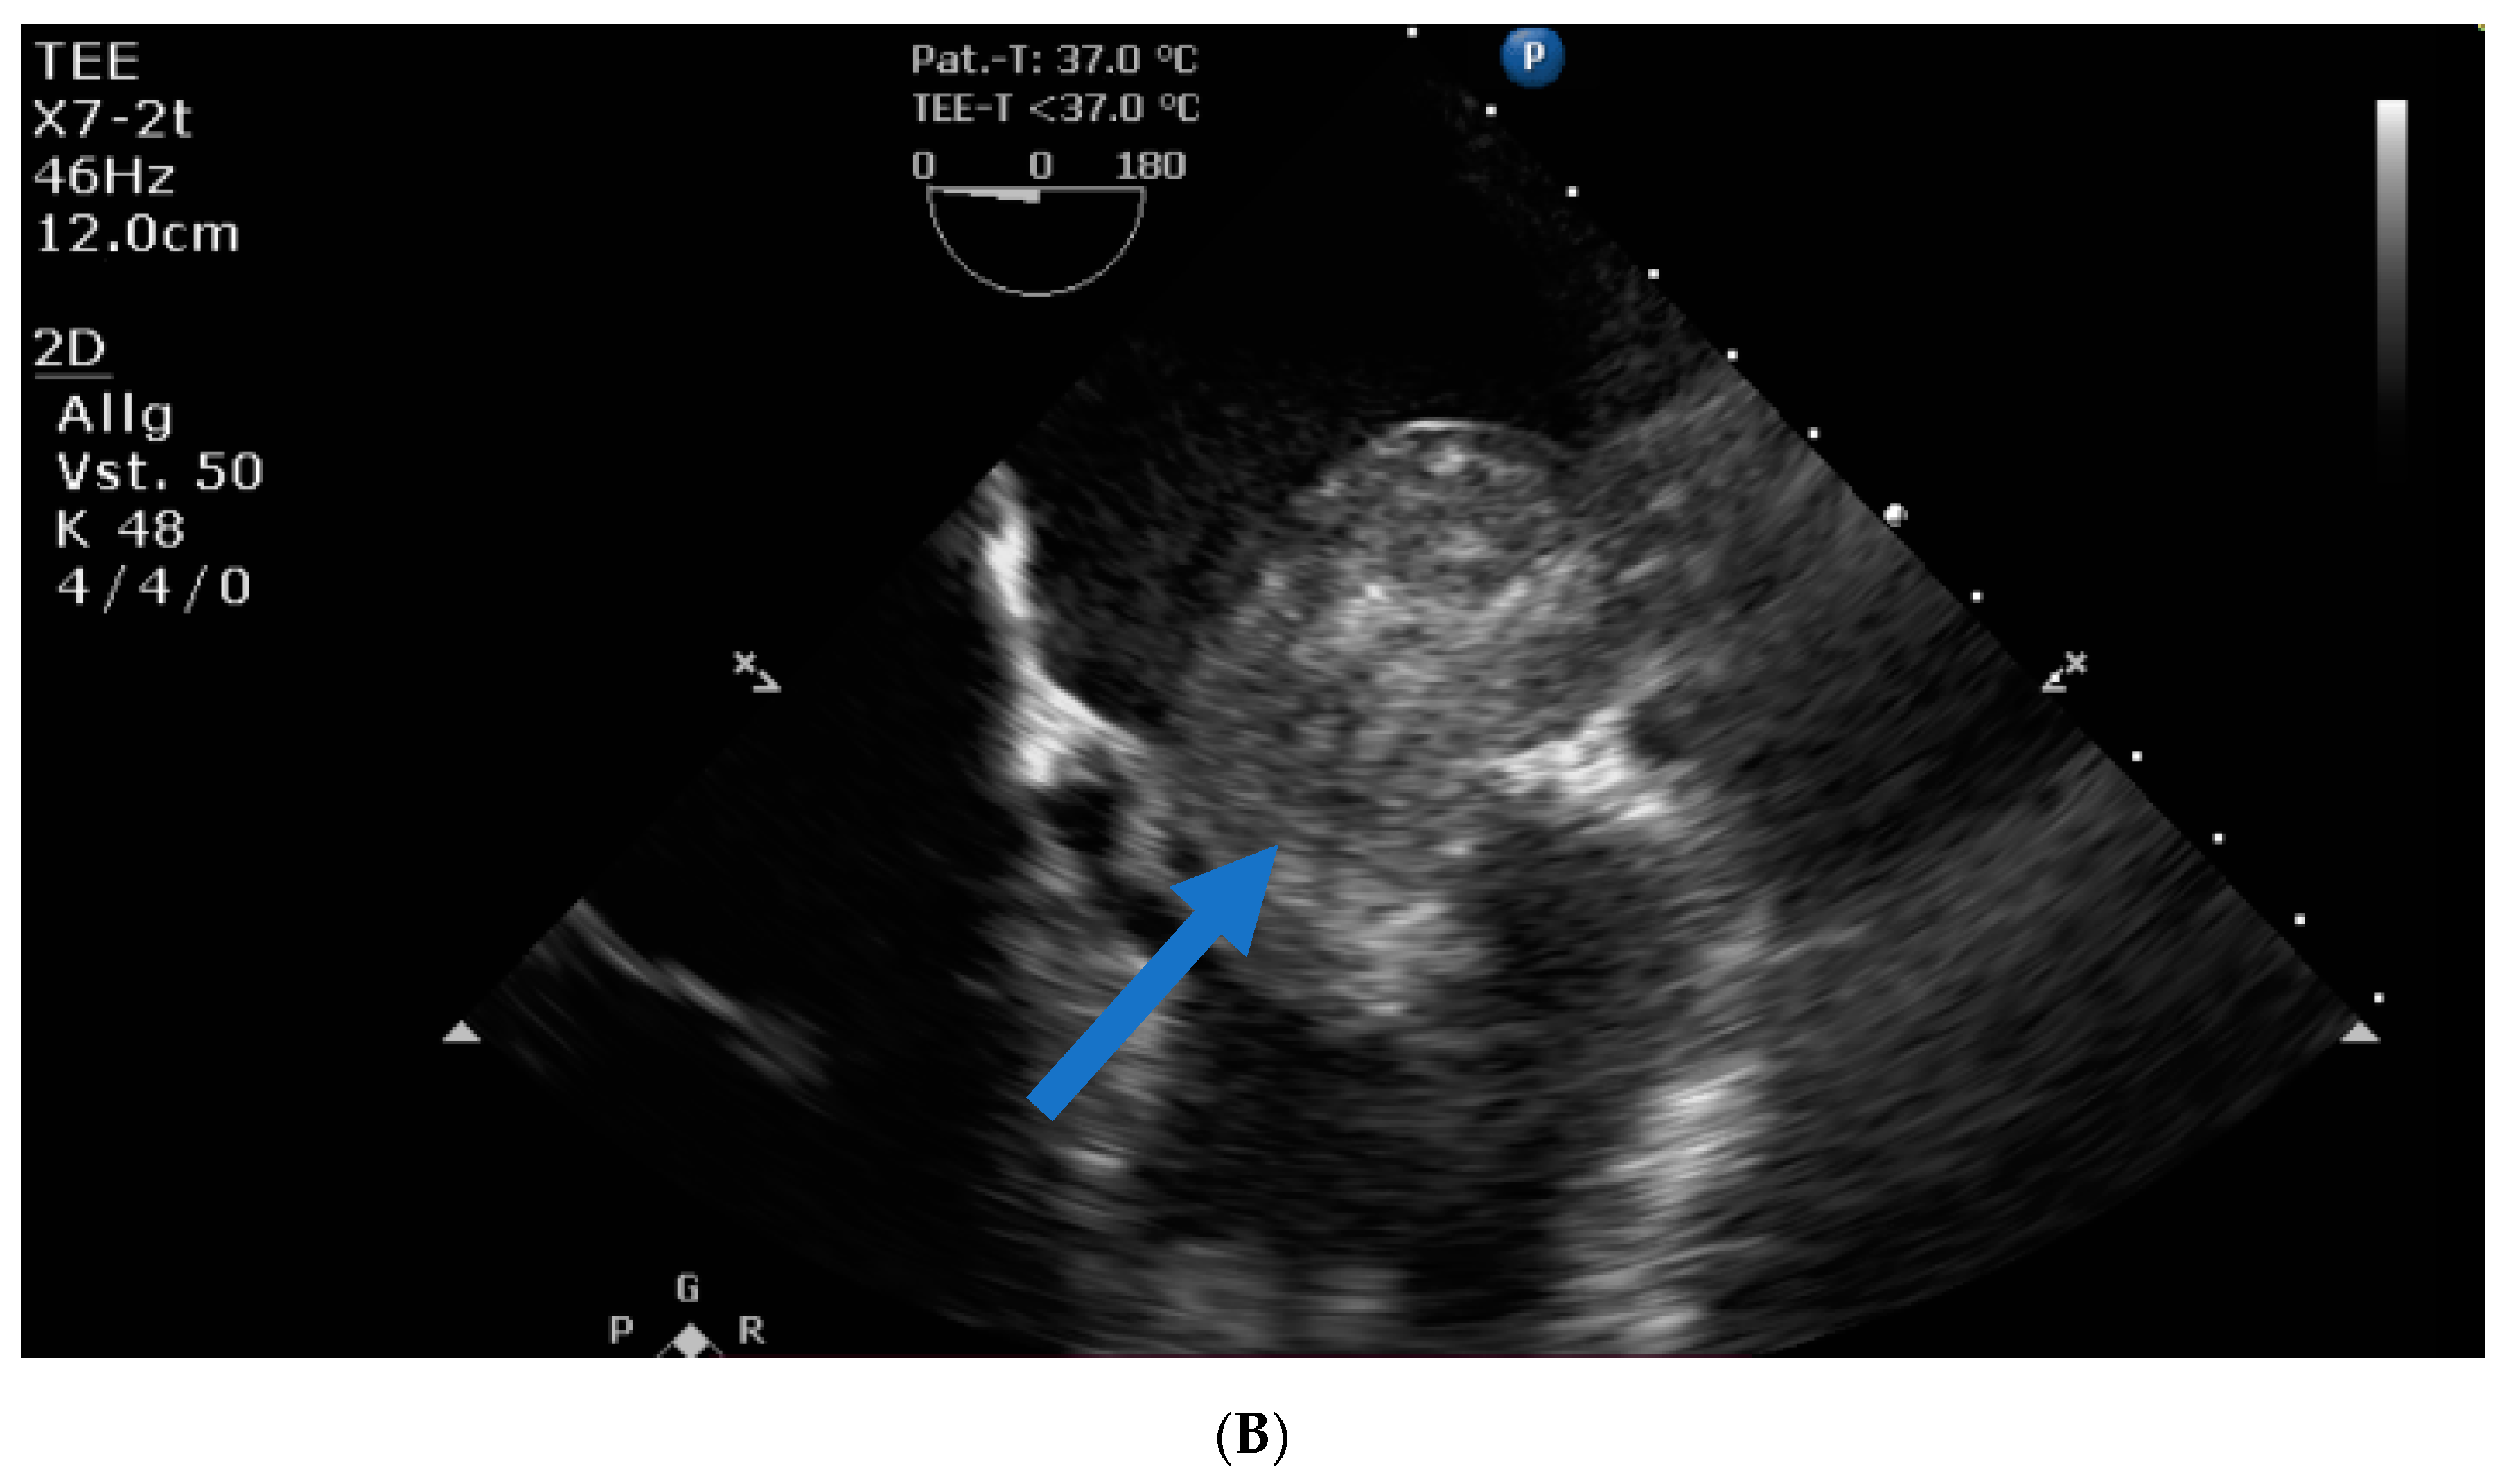

Transthoracic and transesophageal echocardiography revealed a large mass (40 × 60 × 24 mm) in the left atrial lateral wall, extending to the mitral valve (Figure 1A,B). Both atria were severely dilatated. The left ventricle was normal in size with an ejection fraction of 55%, an apicolateral/midlateral hypokinesia and a mild diastolic dysfunction. The normal-sized right ventricle had impaired systolic function. A hemodynamically irrelevant pericardial effusion was present.

Figure 1.

(A) Huge left atrial mass (arrow indicates cardiac mass). (B) Huge left atrial mass prolapsing into the mitral valve in diastole and thus obstructing the inflow of the left ventricle (arrow indicates cardiac mass).